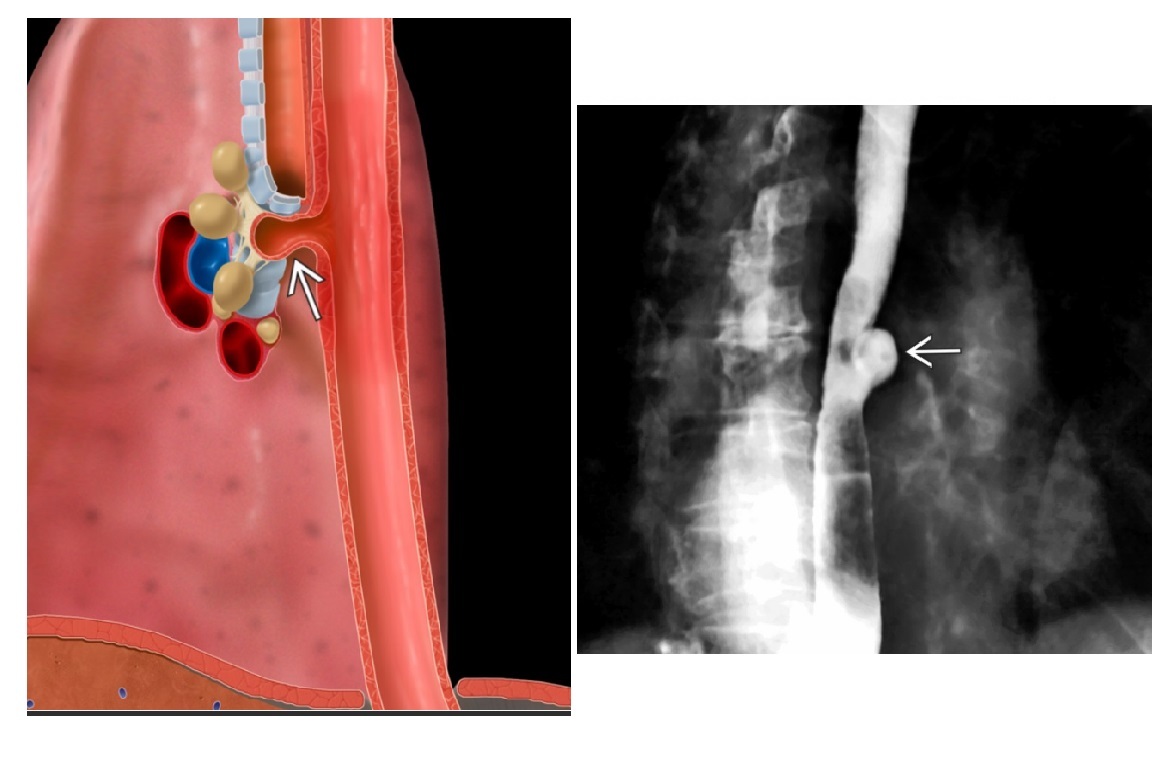

Zenker Diverticulum

Outpouching with rounded contour posteriorly in the neck is above the cricopharyngeus muscle

In hypopharynx!!!

Site of weakness is the Killian dehiscence - between the inferior pharyngeal constrictor muscle and cricopharyngeal muscle